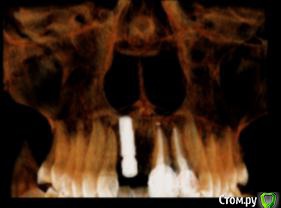

Ната-ли Опубликовано 16 сентября, 2015 Поделиться Опубликовано 16 сентября, 2015 Всем удачного дня!Совсем не знаю как мне быть ?! Просверлили нечаянно корень зуба, пришлось ставить имплант Astra Tech. Имплант стоит уже год. Болел пол года при эмоциональных , физических, психологических нагрузках ))) Имплан мой очень не любил спорт и горячий душ))) Но если просто лежать на диванчике, то имплант чувствовал себя прекрасно. Сумомед и кетанов стали моими неразлучными друзьями.) Кстати, нос тоже болел...наверное и нос как-то нечаянно задели имплантом))) Сейчас вроде по-легче.... Сделала снимок импланта в 3д. Когда расшифровали, я была в полном стрессе... Всё содержимое снимка, с моим вращающем черепом загрузить не получается...вот сделала скрин...(вид с боку)Имплант на 11-ом зубе , впереди держится только за слизистую, судя по снимку кости нет ...куда делась не знаю...то ли ушла куда-то, то ли так имплант вкрутили ...мимо кости???Выпиливать имплант не хочется....я же ещё часть кости потеряю ? Имплант беспокоит иногда (ноет, пульсирует), но я уже привыкла. Десна ушла вверх, может пластику десны сделать? (Хотя ни у кого из моих знакомых ни чего не получилось, слизистая, взятая с нёба , отваливалась вместе с нитками.Десна становилась ещё хуже и выше.)Не думаю, что "нарощенная" десна укрепит имплант ))),... но будет по-эстетичнее какое-то время...но потом десна вероятно снова поднимется, держаться-то ей не на чем )))Короче, что делать с десной не знаю...ПО поводу импланта ??? Думаю поставить пока коронку и посмотреть что будет дальше ? Я передними зубами есть ни чего не буду ))) просто для красоты хотя бы))) И буду ждать когда имплант сам выкрутиться ))) Или как ??? Ссылка на комментарий